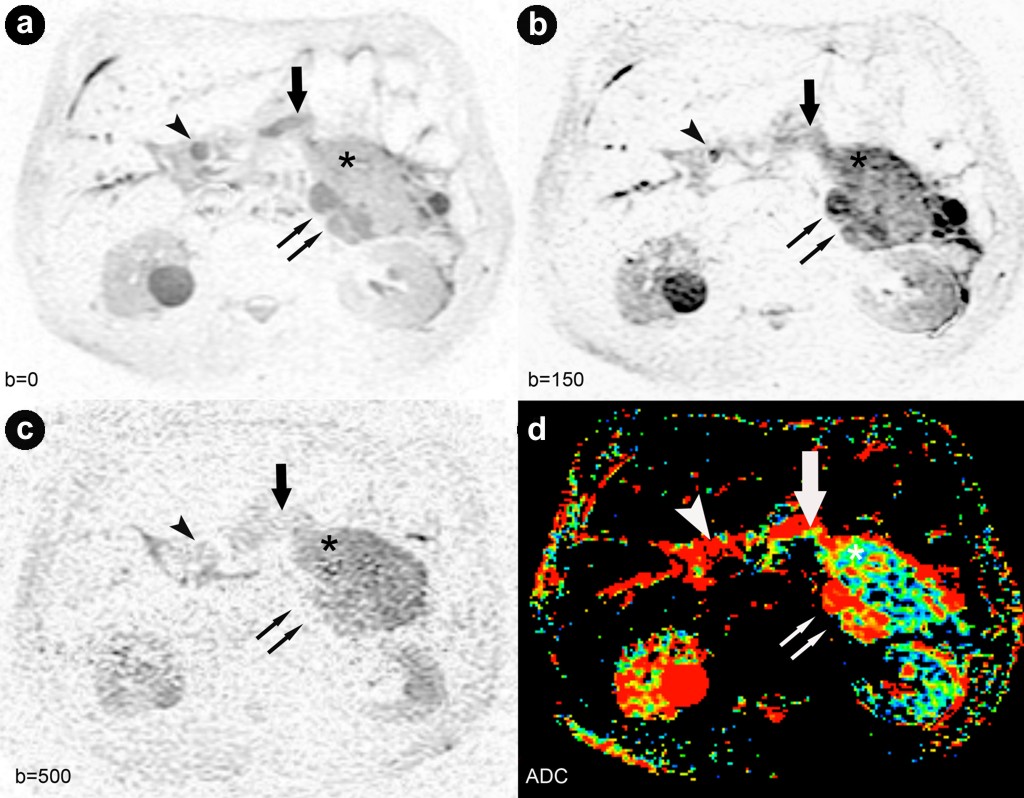

Diffusion-weighted imaging was performed using a diffusion-weighted single-shot echo-planar-imaging sequence with short tau inversion recovery-based fat-suppression. This diffusion-weighted imaging sequence was performed under breath-hold during inspiration. Water diffusion was measured at b-values of 0, 150, 500, and 1,000 s/mm2. Diffusion-weighted imaging visualized the solid tumor parts, the pancreatic duct and the distal common bile duct as well as the cystic parts in the pancreatic head and tail with different intensities up to the b-value used. The signal intensities of all the cystic tumor parts were the highest on diffusion-weighted imaging with lower b-factors. At a higher b-factor (b=500 s/mm2), the signal intensities of the cysts decreased considerably, suggesting a T2 shine-through effect. Apparent diffusion coefficient maps confirmed these findings with high values (0.97x10-3 mm2/s) for all the cystic lesions and low values (0.57x10-3 mm2/s) for the solid tumor parts within the cysts as well as in the pancreatic duct (0.62x10-3 mm2/s) (Figure 3).

Figure 3. Diffusion weighted images at b=0, 150 and 500 s/mm2 and apparent diffusion coefficient-mapping generated from b-values at b=150 s/mm2. a. b. c. Axial diffusion-weighted images displayed with an inverted grey-scale at the level of the pancreatic tail acquired at b=0, 150 and 500 s/mm2. The diffusion-weighted imaging sequences allowed the visualization of the solid tumor parts (asterisk), the pancreatic duct (arrow), the distal common bile duct (arrowhead) as well as the cystic parts in the pancreatic tail (double arrow) with different intensity. Signal intensities of all the cystic tumor parts were highest on diffusion-weighted imaging with b-values at 0 and 150 s/mm2; with a higher b-value of 500 s/mm2, signal intensities of the cysts decreased significantly indicating a T2 shine through effect. d. Apparent diffusion coefficient-maps confirmed the T2 shine-through effect for all cystic lesions (colored red; double arrow) but not for the solid tumor parts within the cystic components and the pancreatic duct (colored blue; asterisk and arrow). Intraductal oncocytic papillary neoplasm in the common bile duct, confirmed pathologically, was not identifiable on apparent diffusion coefficient-mapping (arrowhead). |

In the present case, diffusion-weighted imaging with low and medium b-values (b=150, 500 s/mm2) allowed a clear depiction and differentiation of the solid and cystic tumor parts as compared to the regular pancreatic tissue. The solid tumor parts mostly represent the papillary component of the intraductal oncocytic papillary neoplasm which was also detectable by MRI and CT. This correlated very well with the macropathologic specimen after a total pancreatectomy. In contrast to FDG-PET, we also found low diffusion values in the main pancreatic duct and the distal common bile duct. Yamashita et al. found restricted perfusion in mucine-containing pancreatic cysts as compared to cysts of other origins at a b-value of 300 s/mm2 [24]. Thus, our findings indicate mucin or papillary tumor components filling the pancreatic duct system and the distal common bile duct. This is the first intraductal oncocytic papillary neoplasm case study which includes diffusion-weighted imaging. Only one recent study evaluated diffusion-weighted imaging in IPMNs and showed no restricted diffusion, indicating its feasibility in differentiating these two entities [25].

All cystic tumor parts as well as the coexisting right-sided kidney cysts showed higher intensity on diffusion-weighted imaging (b=150 s/mm2) as compared to the solid tumor nodules, with slightly less intensity on b=500 s/mm2, indicating a strong T2 shine-through effect. Apparent diffusion coefficient maps confirmed the T2 shine-through effect by showing high values for all cystic parts and low values for the solid tumor part [26]. In a recent study, significant differences between the signal intensity ratios of pancreatic cystic lesions were found on images at a b factor of 1,000 s/mm2, making the differentiation of pancreatic cysts possible [27]. However, with a higher b factor (b =1,000 s/mm2), we obtained a very low signal-to-noise ratio causing anatomic distortion due to susceptibility effects which did not allow diagnostic image interpretation. This is a well-known problem for echo-planar sequences with higher b-values resulting in greater image distortion [28].